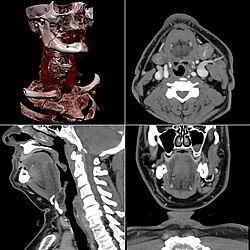

Craniale Computertomographie Abgebildet sind Felsenbein und Nasennebenhöhlen. Aufgrund der hohen Auflösung der Aufnahme des verwendeten 64-Zeilen-CTs sind selbst die Gehörknöchelchen erkennbar. -

Koronal reformatierte Darstellung von Abdomen und Becken; gut zu erkennen sind u. a. die Leber und die beiden Nieren. -

Kombination aus multiplanarer Reformatierung und sliding thin slab. Der Bildkursor befindet sich in der Harnblase. Die Originalschichtdicke beträgt 1,25 mm, dargestellt wird in allen Ansichten gemittelt (= average) in 3,7 mm bzw. 3,8 mm Dicke. -

Kombination aus multiplanarer Reformatierung und sliding thin slab. Der Bildkursor befindet sich im rechten Lungenflügel. Die sts-Bildstapel werden in Form von MIP-Darstellungen gezeigt (STS-MIP).[52] Links oben befindet sich eine VR-Darstellung der Lunge; sie zeigt einen Blick auf die koronal an Kursorposition geschnittene Lunge. -

CT-Angiographie; mittels multiplanarer Reformation (hier die sog. curved MPR) sind auch Schnittdarstellungen entlang beliebiger Gefäßverläufe möglich, wodurch die gezeigte Arteriosklerose sehr gut visualisiert werden kann.